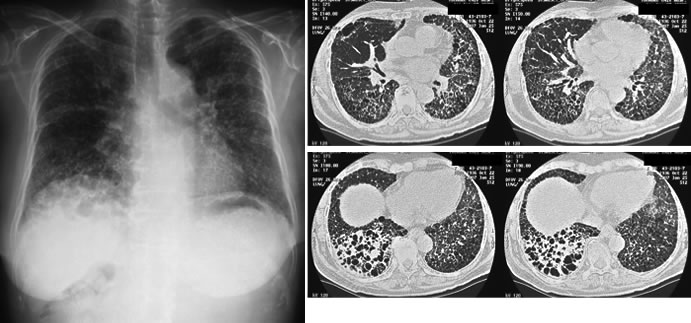

免疫力のない方で問題となる真菌(アスペルギルス感染症)(図7, 8)やニューモシスチス肺炎(図9)に対しては、当科研究室独自に抗体検査や核酸増幅検査を行い、迅速な診断・治療に努めております。国内の研究・検査機関とも協力し、稀な真菌・抗酸菌感染症についても、病原体の同定・診断を試みております(図10) 。

図10. 非結核性抗酸菌症のCT画像。両方の肺に小さな粒状の陰影と空洞を認め、喀痰検査からはM.aviumが検出されました。